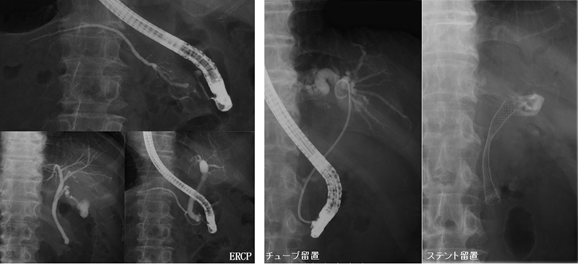

多目的デジタルX線TV装置を用いた胆道系検査・治療、肝腫瘍に対する血管造影検査・治療等を医師、看護師とともにチームで取り組んでいます。